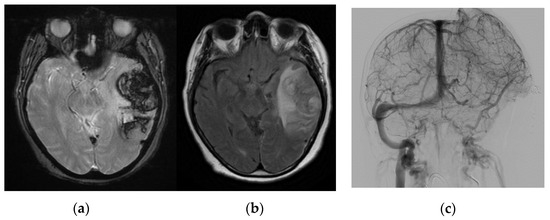

| F | 61 | No | No | 15 | Thrombosis in multiple sinuses (internal cerebral vein, Galen vein, right sinus, torcula, left lateral sinus) | LMWH, craniectomy, thrombectomy | Epilepsy | Death |

| F | 54 | No | Previous cancer, under Tamoxifen | 0 | Left transverse and sigmoid sinus thrombosis, with left temporal and parietal hemorrhagic infarct | LMWH | Neuropsychiatric alterations | Transferred to Psychiatry, not fully recovered. Persistence of cognitive disorders. |